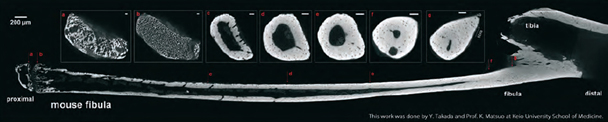

Kính hiển vi cắt lớp nano3DX là một thiết bị lý tưởng cho phân tích các mẫu xương ở độ phân giải dưới micro. Một trong những tính năng quan trọng của nano3DX là khả năng quan sát các mẫu lớn ở độ phân giải cao. Trong ví dụ dưới đây, toàn bộ xương mác chuột đã được phân tích bằng nano3DX, lần đầu tiên một phân tích toàn bộ xương đã được thực hiện.

Hình học tia song song và khả năng của 3D nano để có được hình ảnh có độ tương phản cao nhanh chóng cho phép đối với các bộ sưu tập của tomogram đầy xương từ gần đến xa tận cùng. Với mỗi lát, các cấu trúc trong xương có thể thấy rõ, bao gồm sụn mềm ở đầu gần. Các quán bar quy mô là 50 mm dài trong mỗi insets và xương chính nó là dài khoảng 12 mm. Tủy xương, microvessels và osteocyte thiếu sót được mô tả rõ ràng.